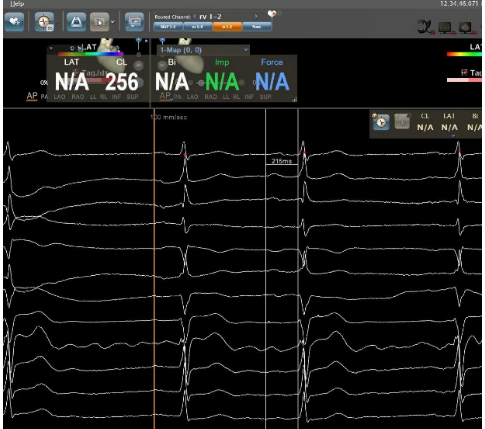

自身:P波宽度96ms,PR间期215ms

Bachmann束区域起搏:P波宽度75ms,PR间期185ms